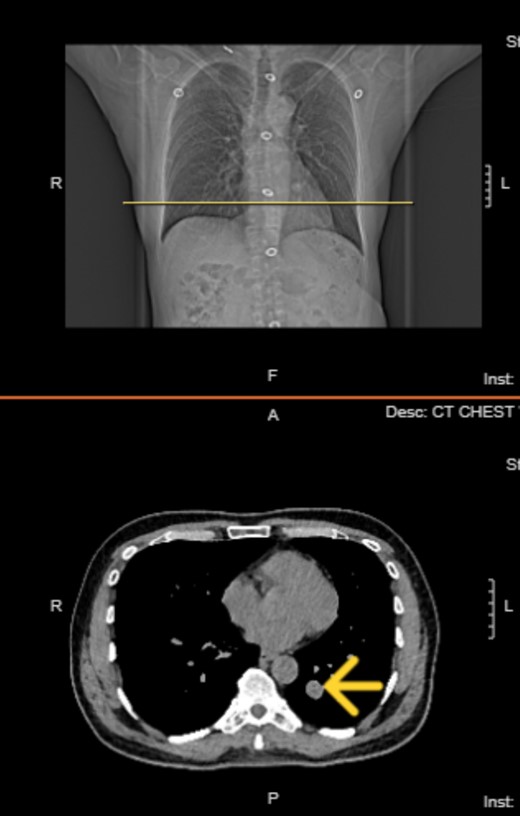

The patient is a 57-year-old male in the United States, who is a non-smoker with good past health. He had no history of occupational exposure to silica, beryllium, or asbestos. He presented with fever and dyspnea and attended the ER, where he was diagnosed with COVID-19 infection and a lung nodule. He underwent a computed tomography (CT) scan of the chest as a part of their diagnostic workup for suspected COVID-19 infection. Chest CT on 21 May 2021 revealed the presence of a well-demarcated non-calcified solid nodule of 1.5 × 1.3 cm in the left lower lobe of the lung (Fig. 1). It was suspected to be a lung carcinoma at first. CT-guided lung biopsy was recommended for further diagnosis.

Chest computed tomography in 2022 revealed well circumscribed solitary lung tumor of 1.5 × 1.3 cm in size.

Top image: Coronal view indicating the level of the solitary fibrous tumor (SFT). Bottom image: Axial CT scan at the indicated level, showing a well-circumscribed, homogeneous mass.